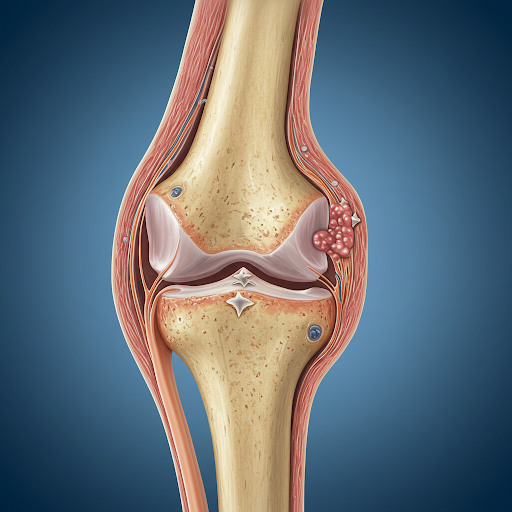

주로 30~50대 여성에게 많이 나타나며, 유전적 요인도 작용합니다. - 퇴행성 관절염은 노화나 과사용으로 인해 관절 연골이 닳아 생기는 질환입니다.

나이가 들수록 누구에게나 발생할 수 있으며, 특히 무릎, 고관절, 허리 등 체중을 많이 받는 부위에 잘 생깁니다.

- 퇴행성 관절염은 X-ray를 통해 관절 간격이 좁아지거나 뼈의 돌기가 생긴 것을 확인하여 진단합니다.

✔ 퇴행성 관절염 관리와 치료

- 체중 조절이 가장 우선입니다.

무릎이나 고관절에 가해지는 부담을 줄이면 통증도 크게 줄어듭니다. - 운동은 필수지만, 무리하지 않기

관절 주변 근육을 강화시키는 운동이 도움이 됩니다. 대표적으로 실내 자전거, 걷기 등이 있어요. - 약물 치료는 통증 조절을 위한 진통소염제가 주로 사용되며, 경우에 따라 주사 치료나 관절 내시경 치료도 고려됩니다.